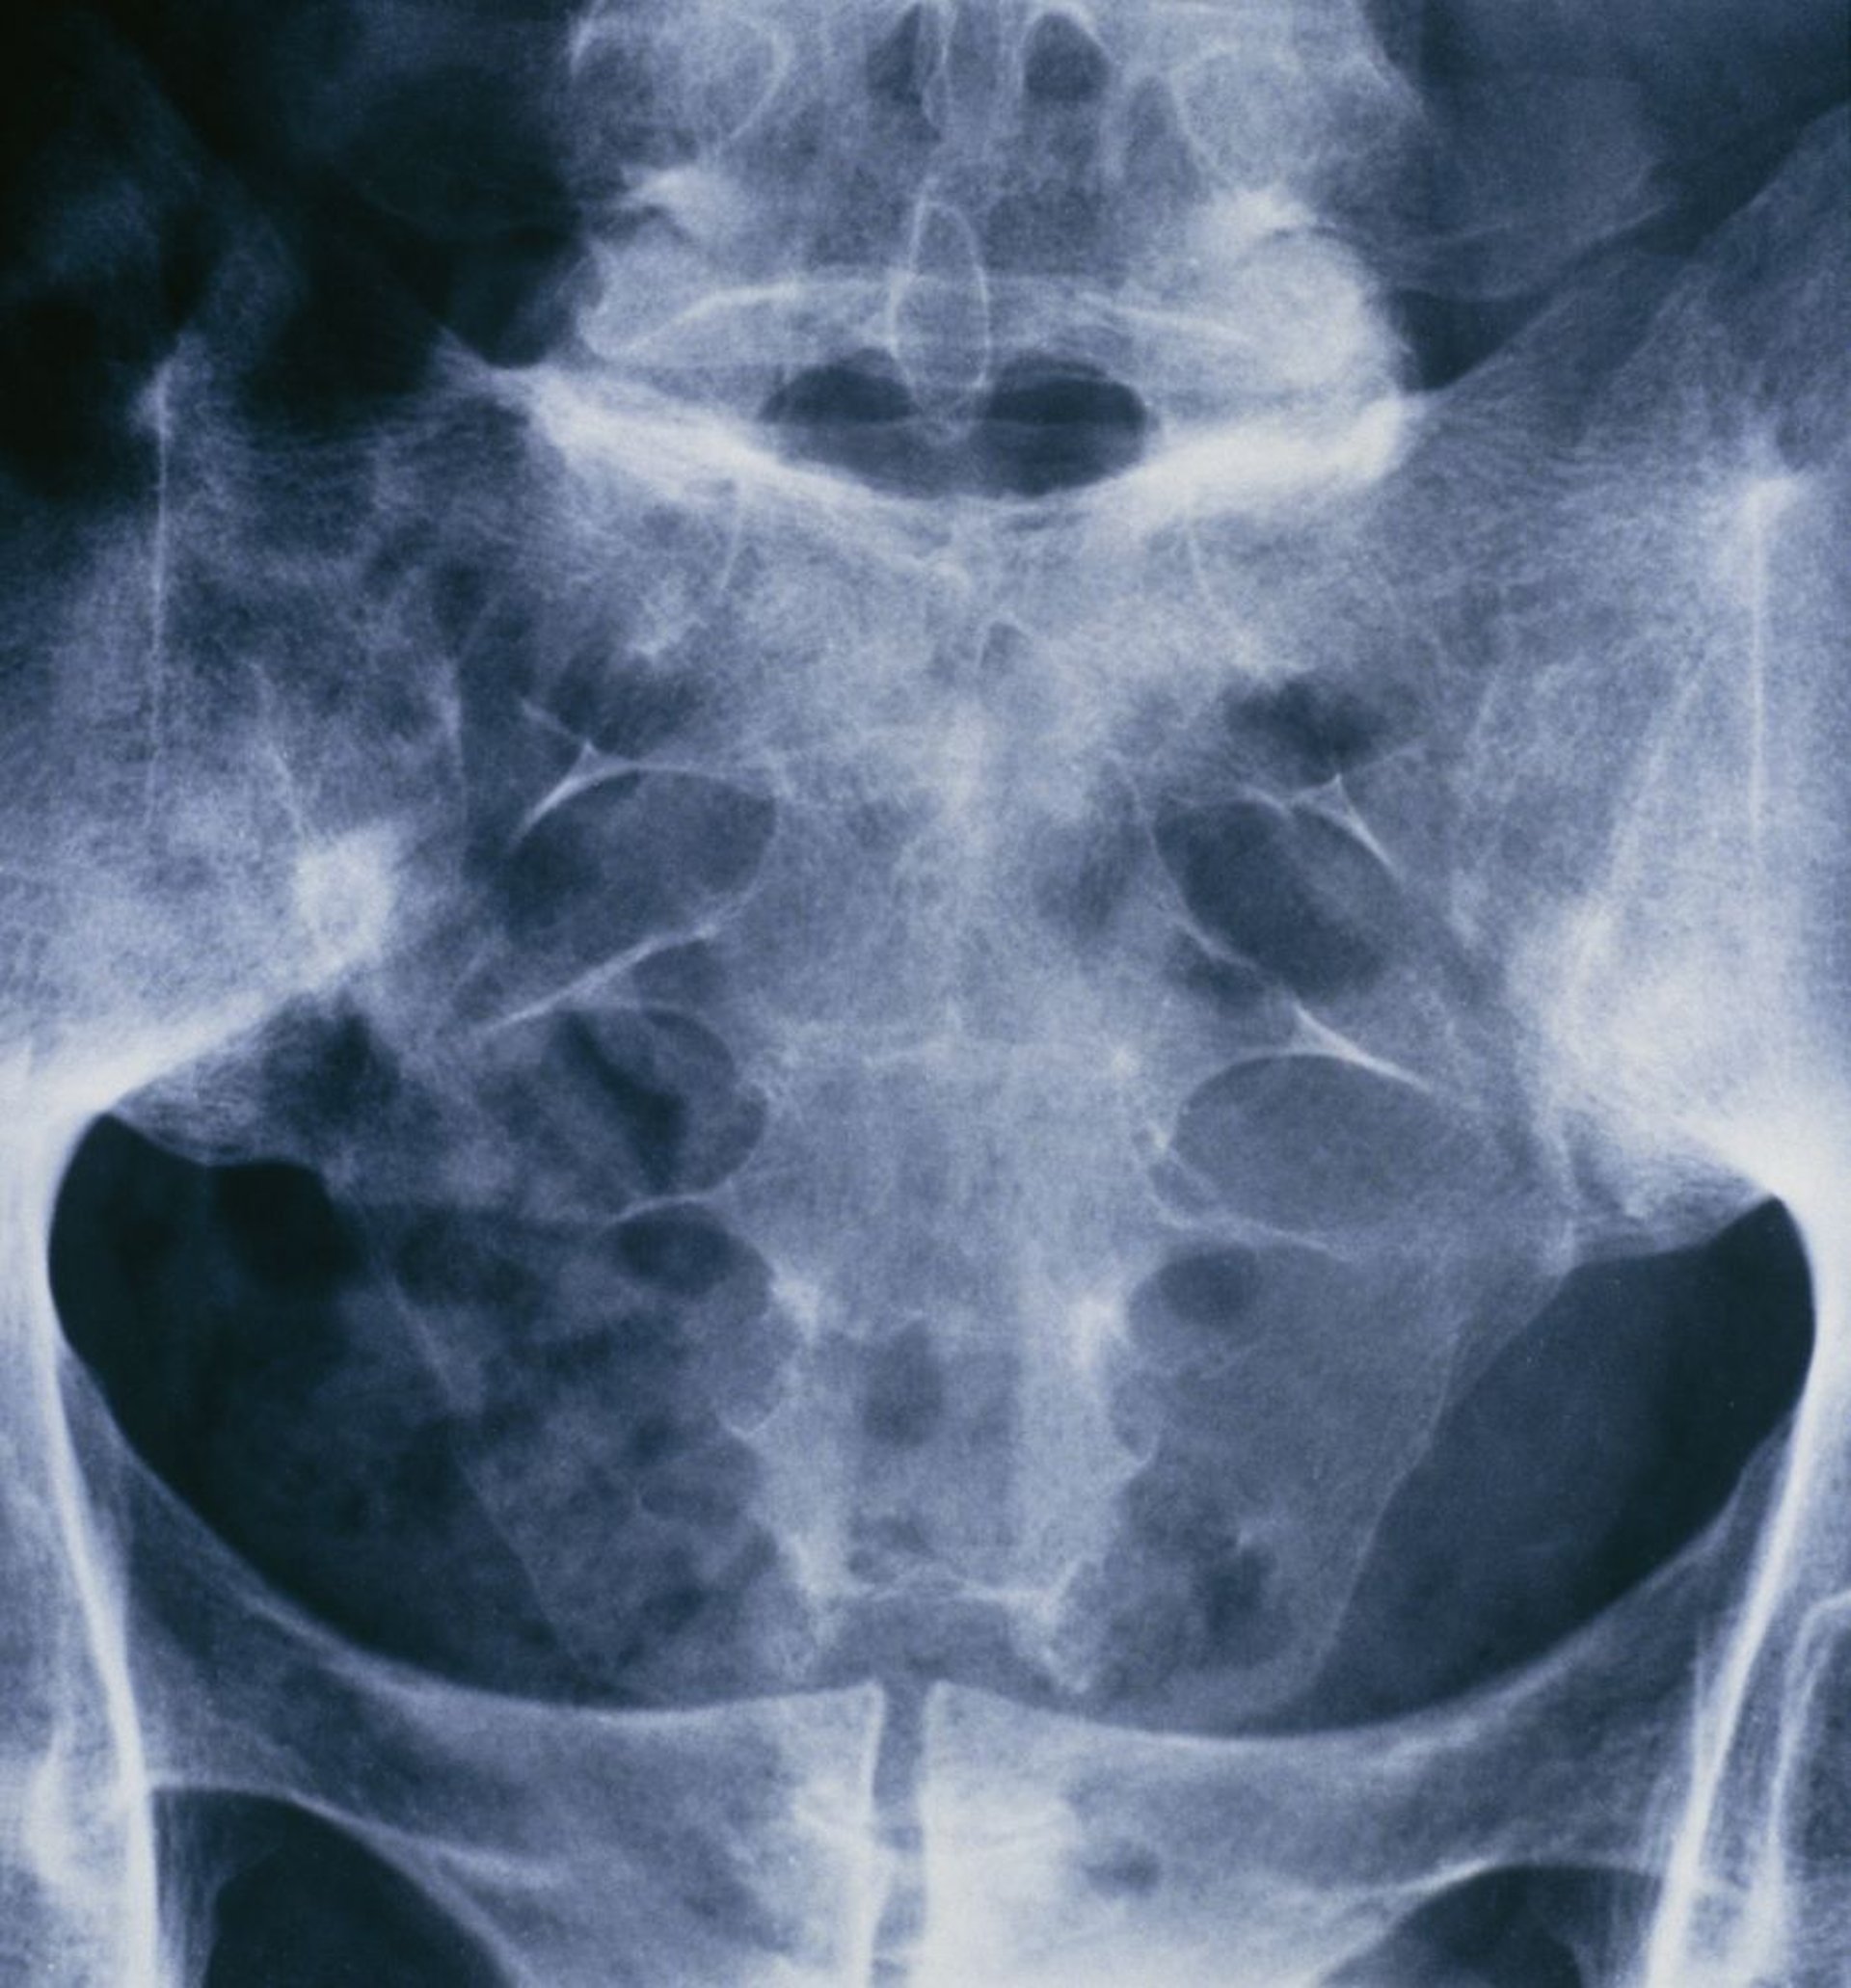

Ankylosing Spondylitis (Sacroiliitis)

This radiograph of the pelvis and sacral spine of a person suffering from ankylosing spondylitis shows fusion of both sacroiliac joints.